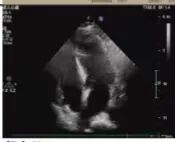

術前超聲

2025年深秋的一個清晨,82歲的馬奶奶(化名)因持續(xù)胸悶氣短被家人送至醫(yī)院心內科。心臟超聲檢查顯示,她的左心房內有一個直徑近5厘米的腫瘤,隨心跳規(guī)律擺動,如同一個隨時可能破裂的“不定時炸彈”。更危急的是,冠脈造影進一步揭示其冠狀動脈多支血管嚴重狹窄,左前降支狹窄達95%,回旋支中段完全閉塞,右冠狀動脈彌漫性病變—兩種致命性心臟疾病的疊加,讓這位高齡患者的生命岌岌可危。

手術當日8時30分,麻醉誘導平穩(wěn)完成。在經食道超聲實時監(jiān)測下,體外循環(huán)管路順利建立,心臟在低溫停跳下顯露術野。主刀醫(yī)生采用“無接觸技術”沿瘤體蒂部完整剝離腫瘤組織,避免碎片脫落;隨后選取左側乳內動脈吻合前降支,大隱靜脈序貫吻合鈍緣支與后降支,完成三支血管重建。125分鐘的轉機時間里,麻醉師全程維持平均動脈壓在65-75mmHg,體外循環(huán)師精準調控流量至2.4L/min/m2。